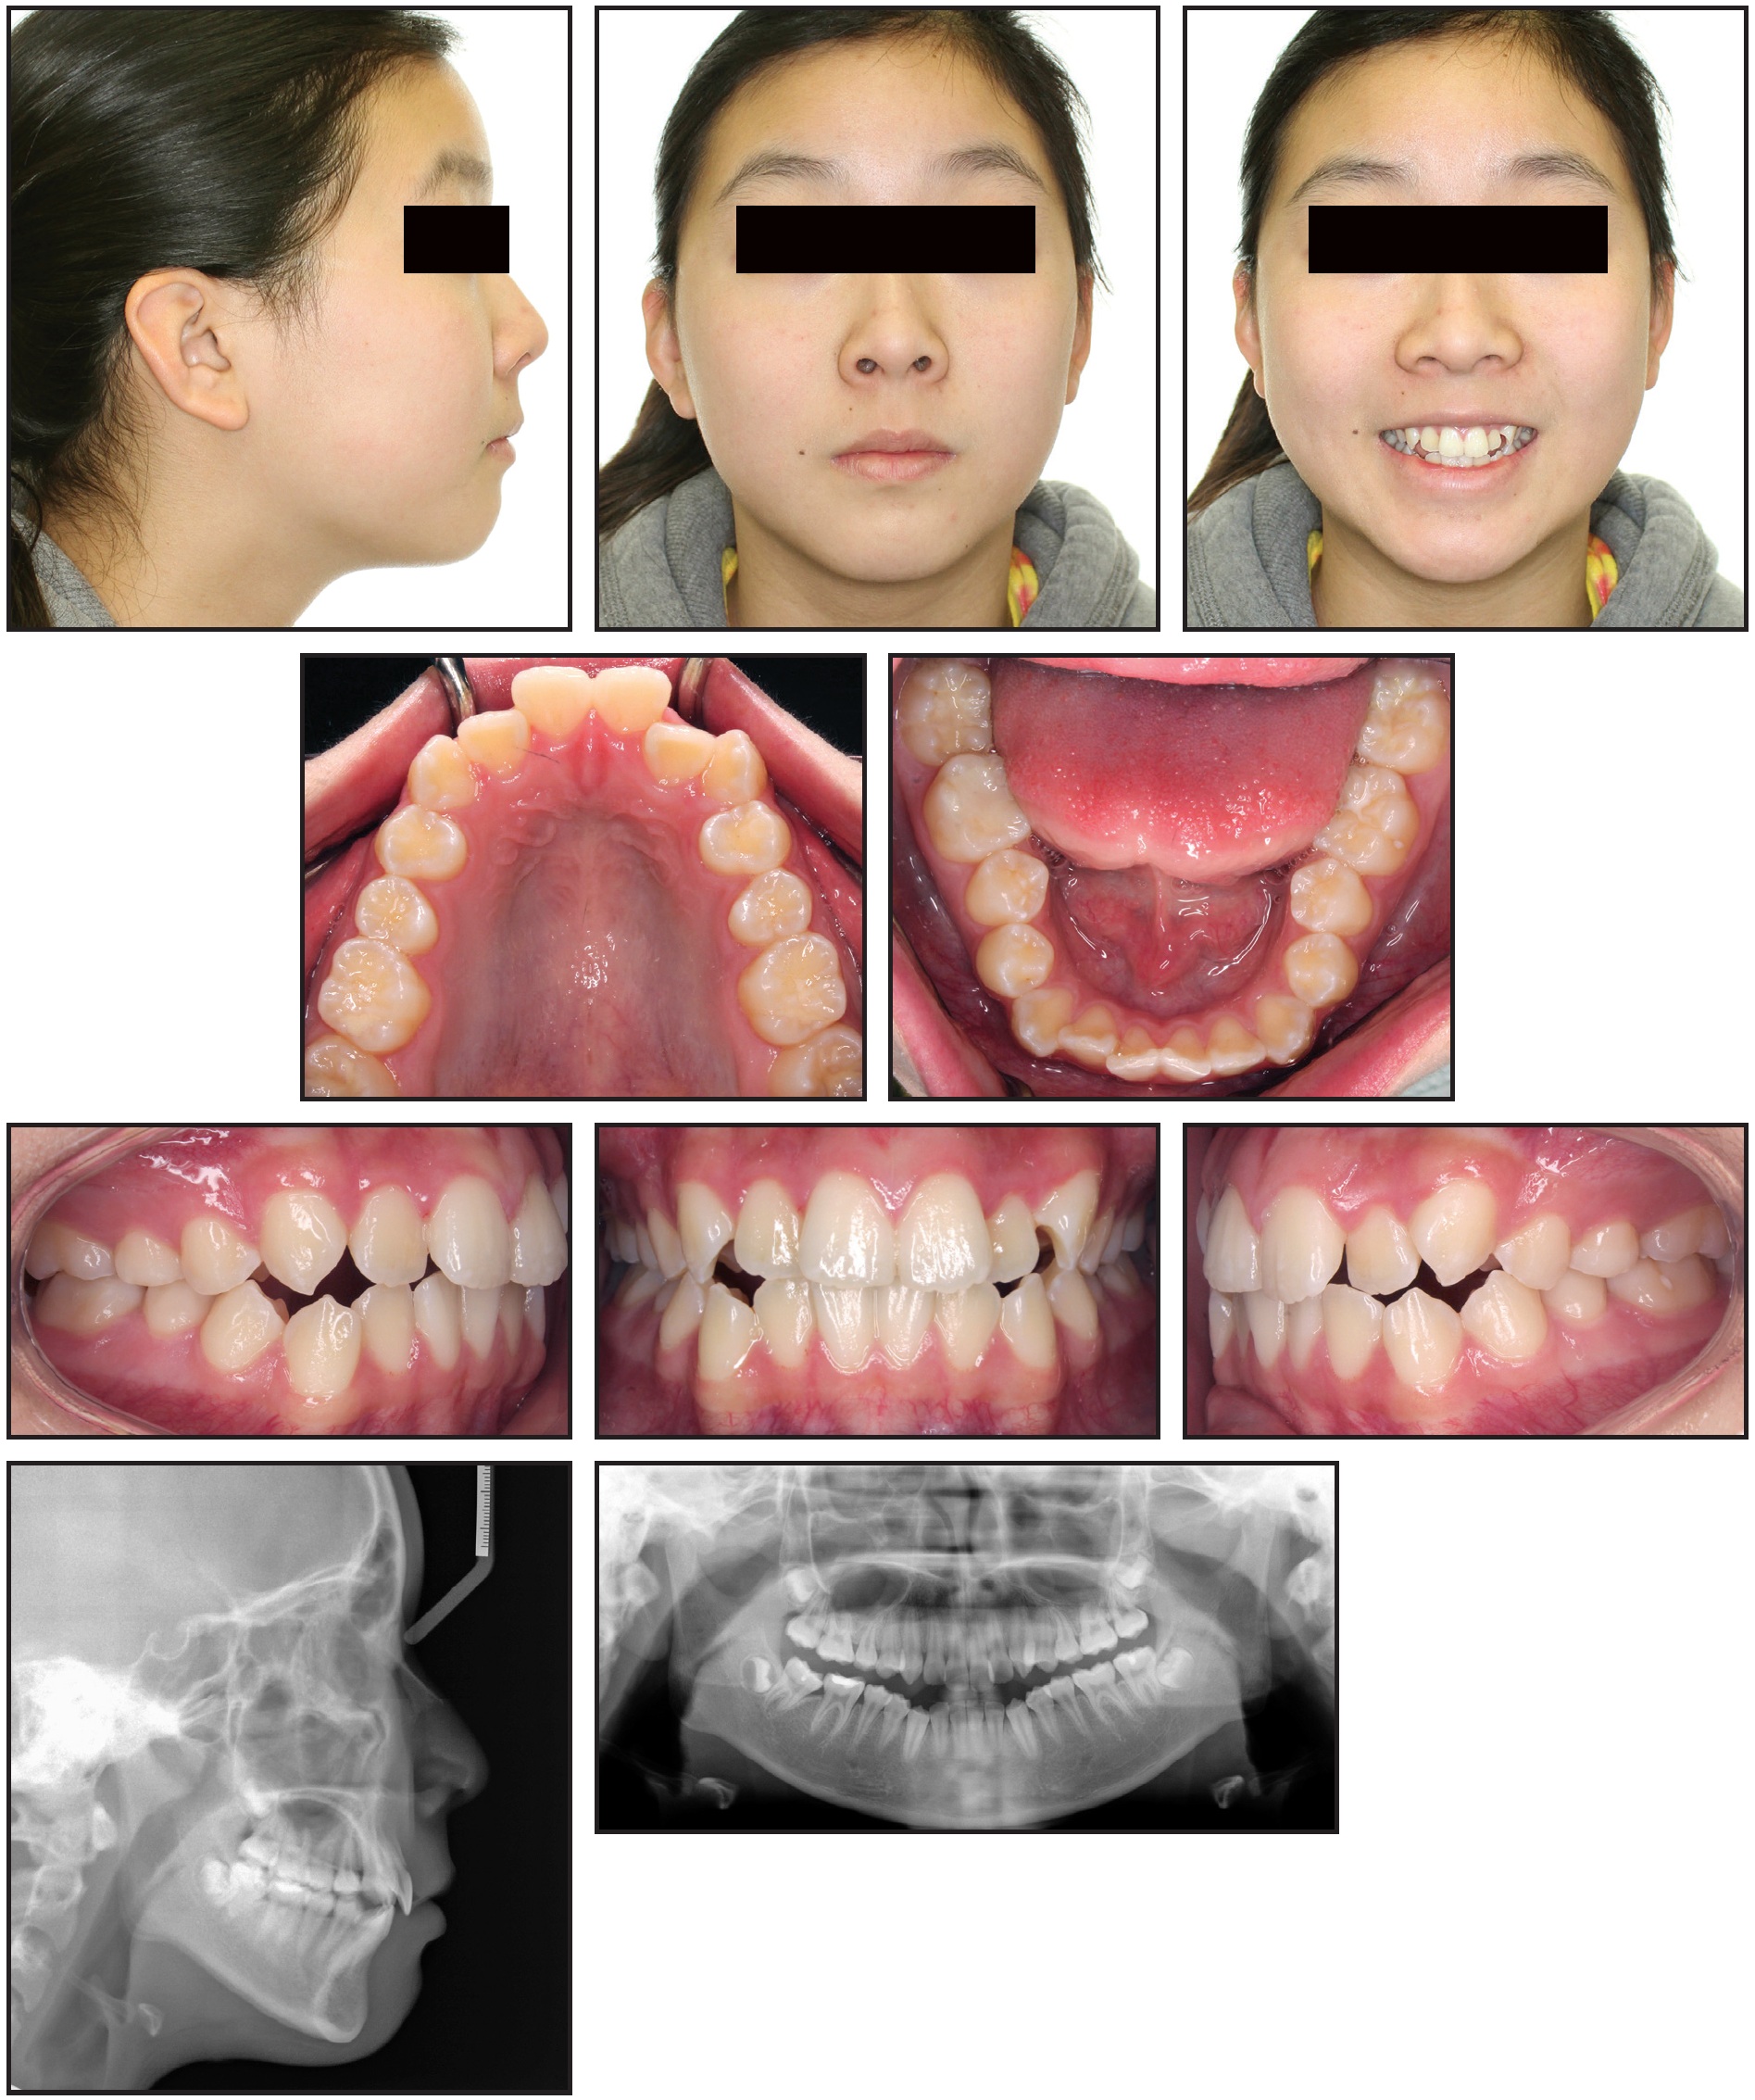

Upper and lower .016" × .022" TMA* archwires were inserted prior to the finishing phase. After 17 months of treatment, we noted an increased gingival display in smiling (3mm), lip incompetency (4mm of lip separation at rest), mentalis muscle strain, and a retrusive chin position (Fig. 2).

Fig. 2 A. After 17 months of leveling and alignment, showing excessive incisor and gingival display, increased interlabial gap, and reduced chin projection, with adequate occlusal relationships. B. Superimposition of pretreatment (black) and progress (blue) cephalometric tracings, confirming backward mandibular rotation and reduced chin prominence.

The lateral cephalometric superimposition showed incisor extrusion and clockwise rotation of the mandible due to vertical growth of the maxilla and slight extrusion of the molars during treatment. The clockwise mandibular rotation had increased the interlabial gap and convexity of the facial profile and reduced the chin projection. After reevaluation, the treatment objectives were to reduce the gingival display and interlabial gap, thus improving smile esthetics, as well as to reduce lower anterior facial height by counterclockwise mandibular rotation and control of maxillary vertical growth.